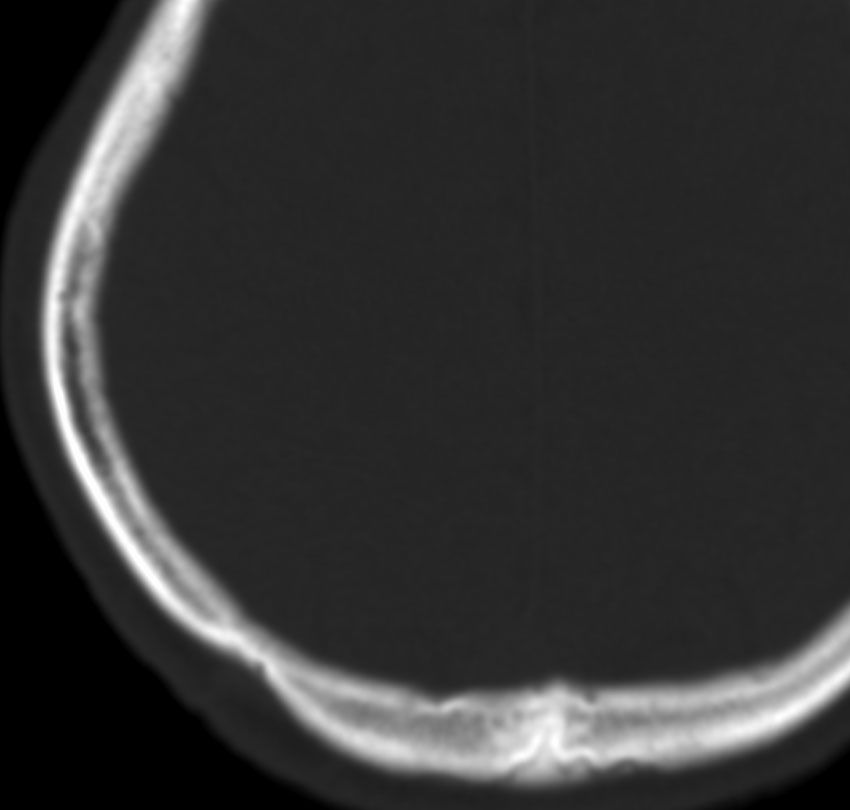

CTで典型的な頭蓋骨の打ち抜き像 punched out lesion が左頭頂骨にあります。これだけでLCHと診断がつくような画像です。

頭蓋骨のLCH

- 上の写真は,子供の右の頭頂骨にできたLCHで,頭部病変では最も多く見られるタイプです

- 頭蓋骨が丸く抜けるように破壊されるのでpunched out lesionと表現されます

- 頭蓋骨欠損がそれほど大きくないものは様子を見ます

- 自然に消失して治ってしまうことも多いです

- 単臓器単発型は無治療で経過をみるというのもよいでしょう